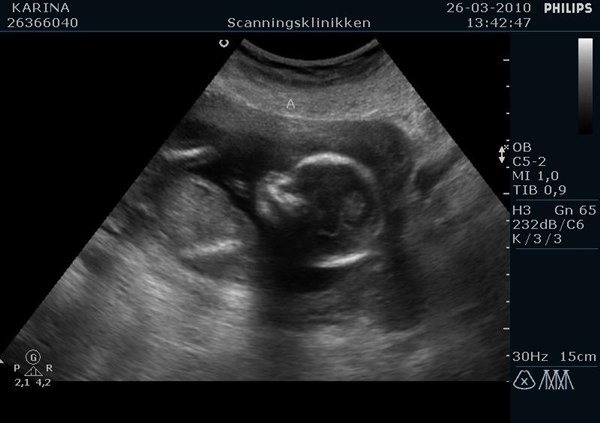

De første billeder er af deres ædler dele. Først fandt hun Viola. Efterfølgende søgt hun længe efter Alvin' s ædler dele. Lige da den var ved at være der, tog han hånden ned og rodede sig lidt i skridtet. Der var vi ikke i tvivl. Det var en dreng. Senere hen så var der næsten en lille tissemand på samtlige billeder. Han skulle bare lige finde ud af, at det var den vi ville se.

De sidste billeder er af de to i profil. Viola hedder A og Alvin hedder B.